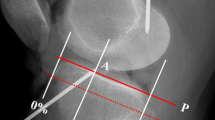

Femoral attachments of the superficial MCL (sMCL), deep MCL (dMCL) and the posterior oblique ligament (POL) as seen radiographically, in relation to the normalisation as a percentage of the AP size of the medial femoral condyle. Note that the wire staples were inserted into the bone with the fold in the staple at the point of interest, and the radiographic study required identification of which end of each staple was the correct measurement point at the surface of the bone (coloured areas). The P-D measurements use the same 100% normalising length as the A-P measurements

Normalised results and coordinate system

With each imaging technique, a two-dimensional sagittal plane coordinate system was created to locate the attachment points on the femur and tibia. Datum points were defined in order to allow normalisation for the overall size of each bone. The datum points of the distal femur were the most anterior, posterior, and distal points of the medial femoral condyle (MFC) (Fig. 1). The datum points of the proximal tibia were the anterior and posterior edges of the medial tibial plateau (MTP) (defined in Fig. 2). The location of each femoral attachment was normalised to the A-P dimension of the MFC (= 100%) and also referenced to the ME, while the tibial attachments were normalised to the A-P dimension of the MTP (= 100%). The A-P sizes of the femoral and tibial condyles were also used to define the P-D (proximal–distal) dimensions. All data were recorded as actual measurements in mm, then normalised to the size of the bone in percentages.

A system for radiographic location of femoral attachment points that is easy to use in the clinic was defined by Schöttle et al. [27]: the points were referenced to a line extending distally from the posterior femoral cortex and to a perpendicular line intersecting the most-posterior/proximal edge of Blumensaat’s line (Fig. 3). The distances were measured perpendicular to the reference lines in A-P and P-D directions, as actual sizes in mm and then were normalised.

Method to define positions radiographically, using datum lines that (1) form an extension of the line of the posterior femoral cortex, and (2) a line perpendicular to the former passing through the most-posterior/proximal point of Blumensaat’s line [27]